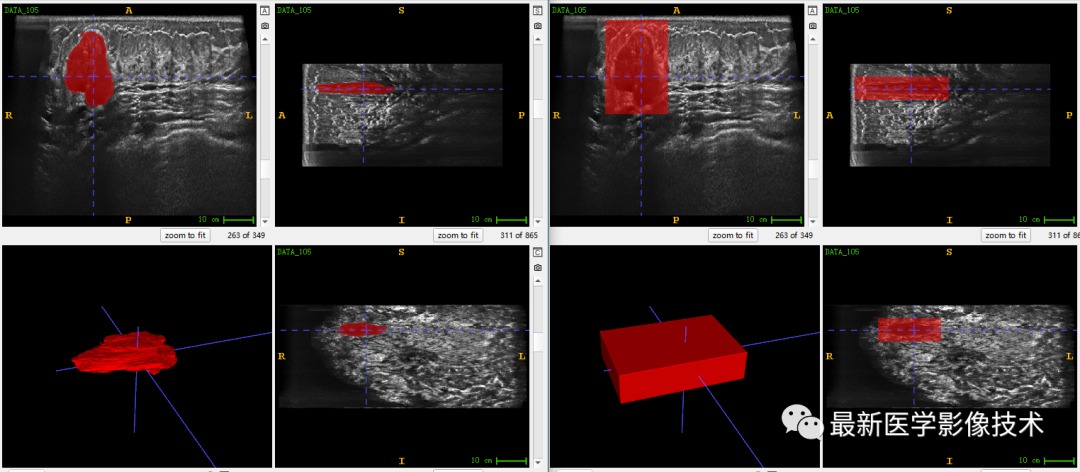

乳腺肿瘤分割采用两阶段分割网络,第一个网络进行粗分割定位肿瘤位置,第二个网络进行精分割得到肿瘤精确轮廓,然后在根据精分割mask和对应ROI图像进行良恶性分类。具体实现可以参考这篇文章TDSC-ABUS2023——2023 年自动化 3D 乳腺超声 (ABUS) 的肿瘤检测、分割和分类挑战.

验证集分割和检测部分结果如下所示。